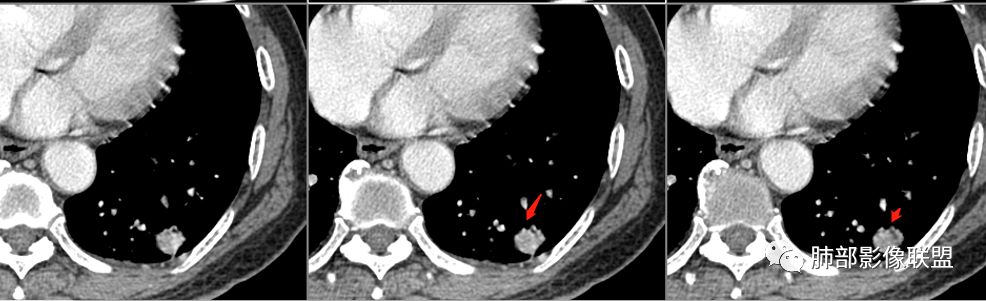

病例2肉瘤样癌的病理意见有些出乎预料,也充分说明病变及影像表现的复杂性。病灶小结节支气管截断、空泡、分叶、短毛刺、血管集束征等似乎均符合肺癌的影像特性。肺鳞癌及肉瘤样癌往往范围较小就可以出现坏死,但如果结节太小则很少能够在影像上观察到坏死区或空洞,没有增强扫描图像更是如此。

支气管截断。

支气管在门口堵塞恶性居多,结核有时也有。

空泡

分叶

血管纠集

毛刺

总体分析,支持恶性。

明日の路过:第二例,患者病灶在左肺上叶,分叶、空泡、血管供养征,感觉跟书上的恶性肿瘤图片一模一样。考虑恶性肿瘤可能。建议全身筛查后直接切除。

晨读二:左肺上叶结节,深分叶,支气管堵塞并挤压,内部可见偏心性空泡,考虑恶性,腺癌,早期鳞癌。

大宝儿.蕊:上叶实性结节,边界清,分叶,短毛刺,小泡征,血管集束征,腺癌首先考虑。